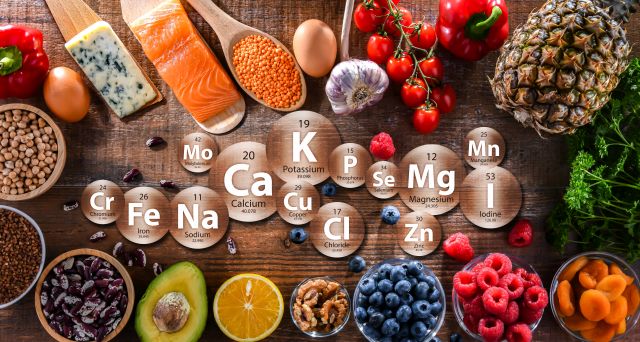

Gendermedizin beschäftigt sich mit den geschlechtsspezifischen Unterschieden in Prävention, Diagnose und Therapie von Krankheiten. Auch in der Ernährung und der Versorgung mit essenziellen Biofaktoren wie Vitaminen und Mineralstoffen spielt die geschlechtersensible Medizin eine zunehmende Rolle, da sich Frauen und Männer in Bezug auf den Nährstoffbedarf unterscheiden können. Gendermedizin berücksichtigt sowohl ...